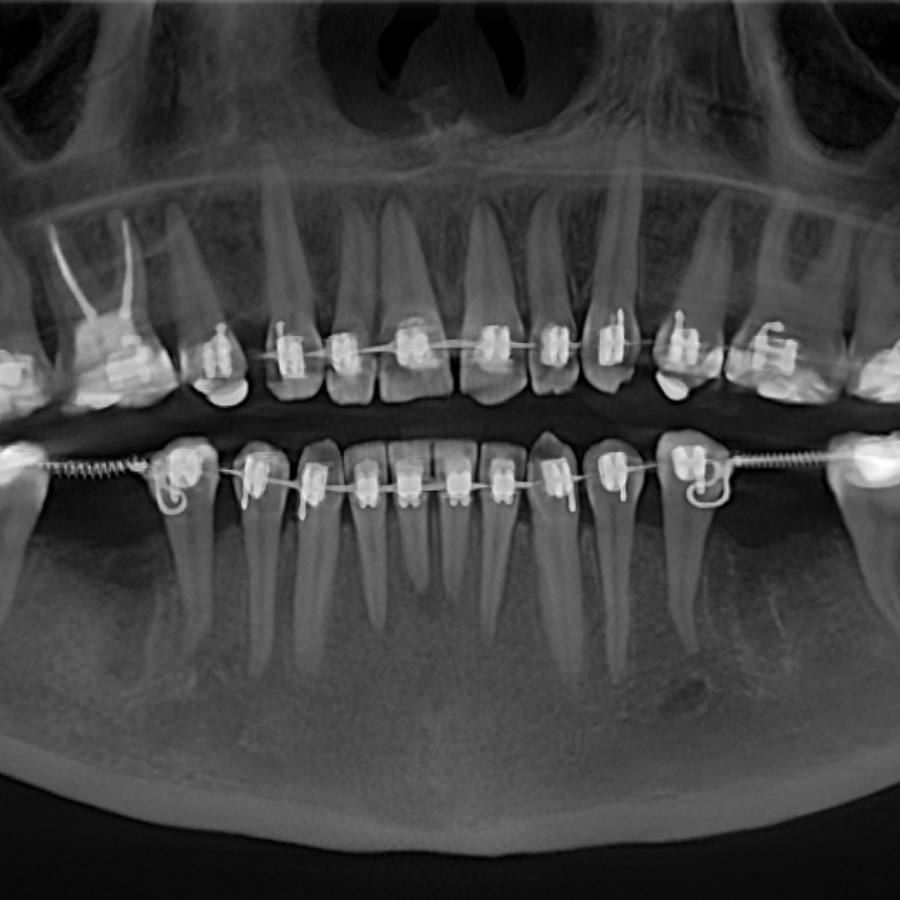

Пациентка начала ортодонтическое лечение и за 5 месяцев до окончания лечения ей удалили нижние шестерки и поставили импланты. За месяц до конца лечения установили формирователи десны. На момент снятия брекетов были сняты слепки под постоянные коронки на имплантатах.

В этом случае одновременно пациент закончил ортодонтическое, хирургическое и ортопедическое лечение. Что возможно только при одновременном подходе команды врачей.

Результат лечения